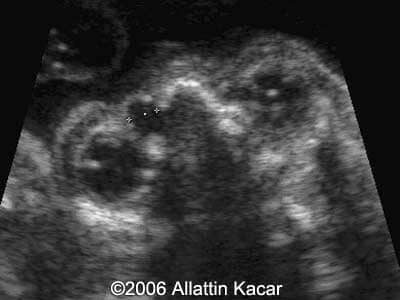

Dacryocystocele Alaattin Kacar, MD Burhan Seker, MD Ender Birgul, MD Ozcan Yilmaz, MD Article Published: May 23, 2006 Turkey This is a case of a dacryocystocele. Discussion Board Start a discussion about this article Add to Favorites Favorite